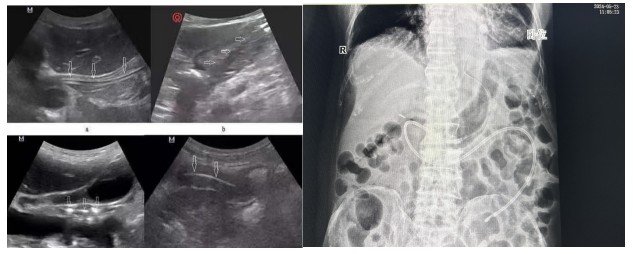

通訊員陽琦珂報道:近日,83歲高齡的李爺爺因“重癥肺炎、呼吸衰竭”入住衡陽市中心醫(yī)院重癥醫(yī)學二科。李爺爺意識為昏睡狀,經氣管切開后長期不能經口進食,為有效解決李爺爺營養(yǎng)保障這一大難題,科室主任劉洋、護士長肖芳共同為患者進行了整體、精準的營養(yǎng)評估,考慮到患者高齡且基礎疾病較多,經過細致的床旁體查,認為患者符合鼻空腸管的置入條件,在排除操作禁忌癥后,主管護師黃云在床旁B超引導下成功為李爺爺進行鼻空腸管置入術。

經腹部X片驗證一個完美的大“C”呈現(xiàn)出來,確認鼻空腸管已經達到指定位置。

B超引導下營養(yǎng)管置入術相比內鏡輔助下營養(yǎng)管置入,通過二維顯像觀察鼻腸管的位置,無創(chuàng)監(jiān)測,定位準確,提高了置管的成功率,能有效減少置管給病人帶來的不適體驗及不必要的損傷。營養(yǎng)支持已成為重癥患者綜合治療重要環(huán)節(jié),對重癥患者預后起著關鍵作用,新喂養(yǎng)途徑的建立,讓腸內營養(yǎng)支持順利的開展,不僅減少了患者的痛苦,也為重癥營養(yǎng)支持治療開辟了一條嶄新的補給通道。